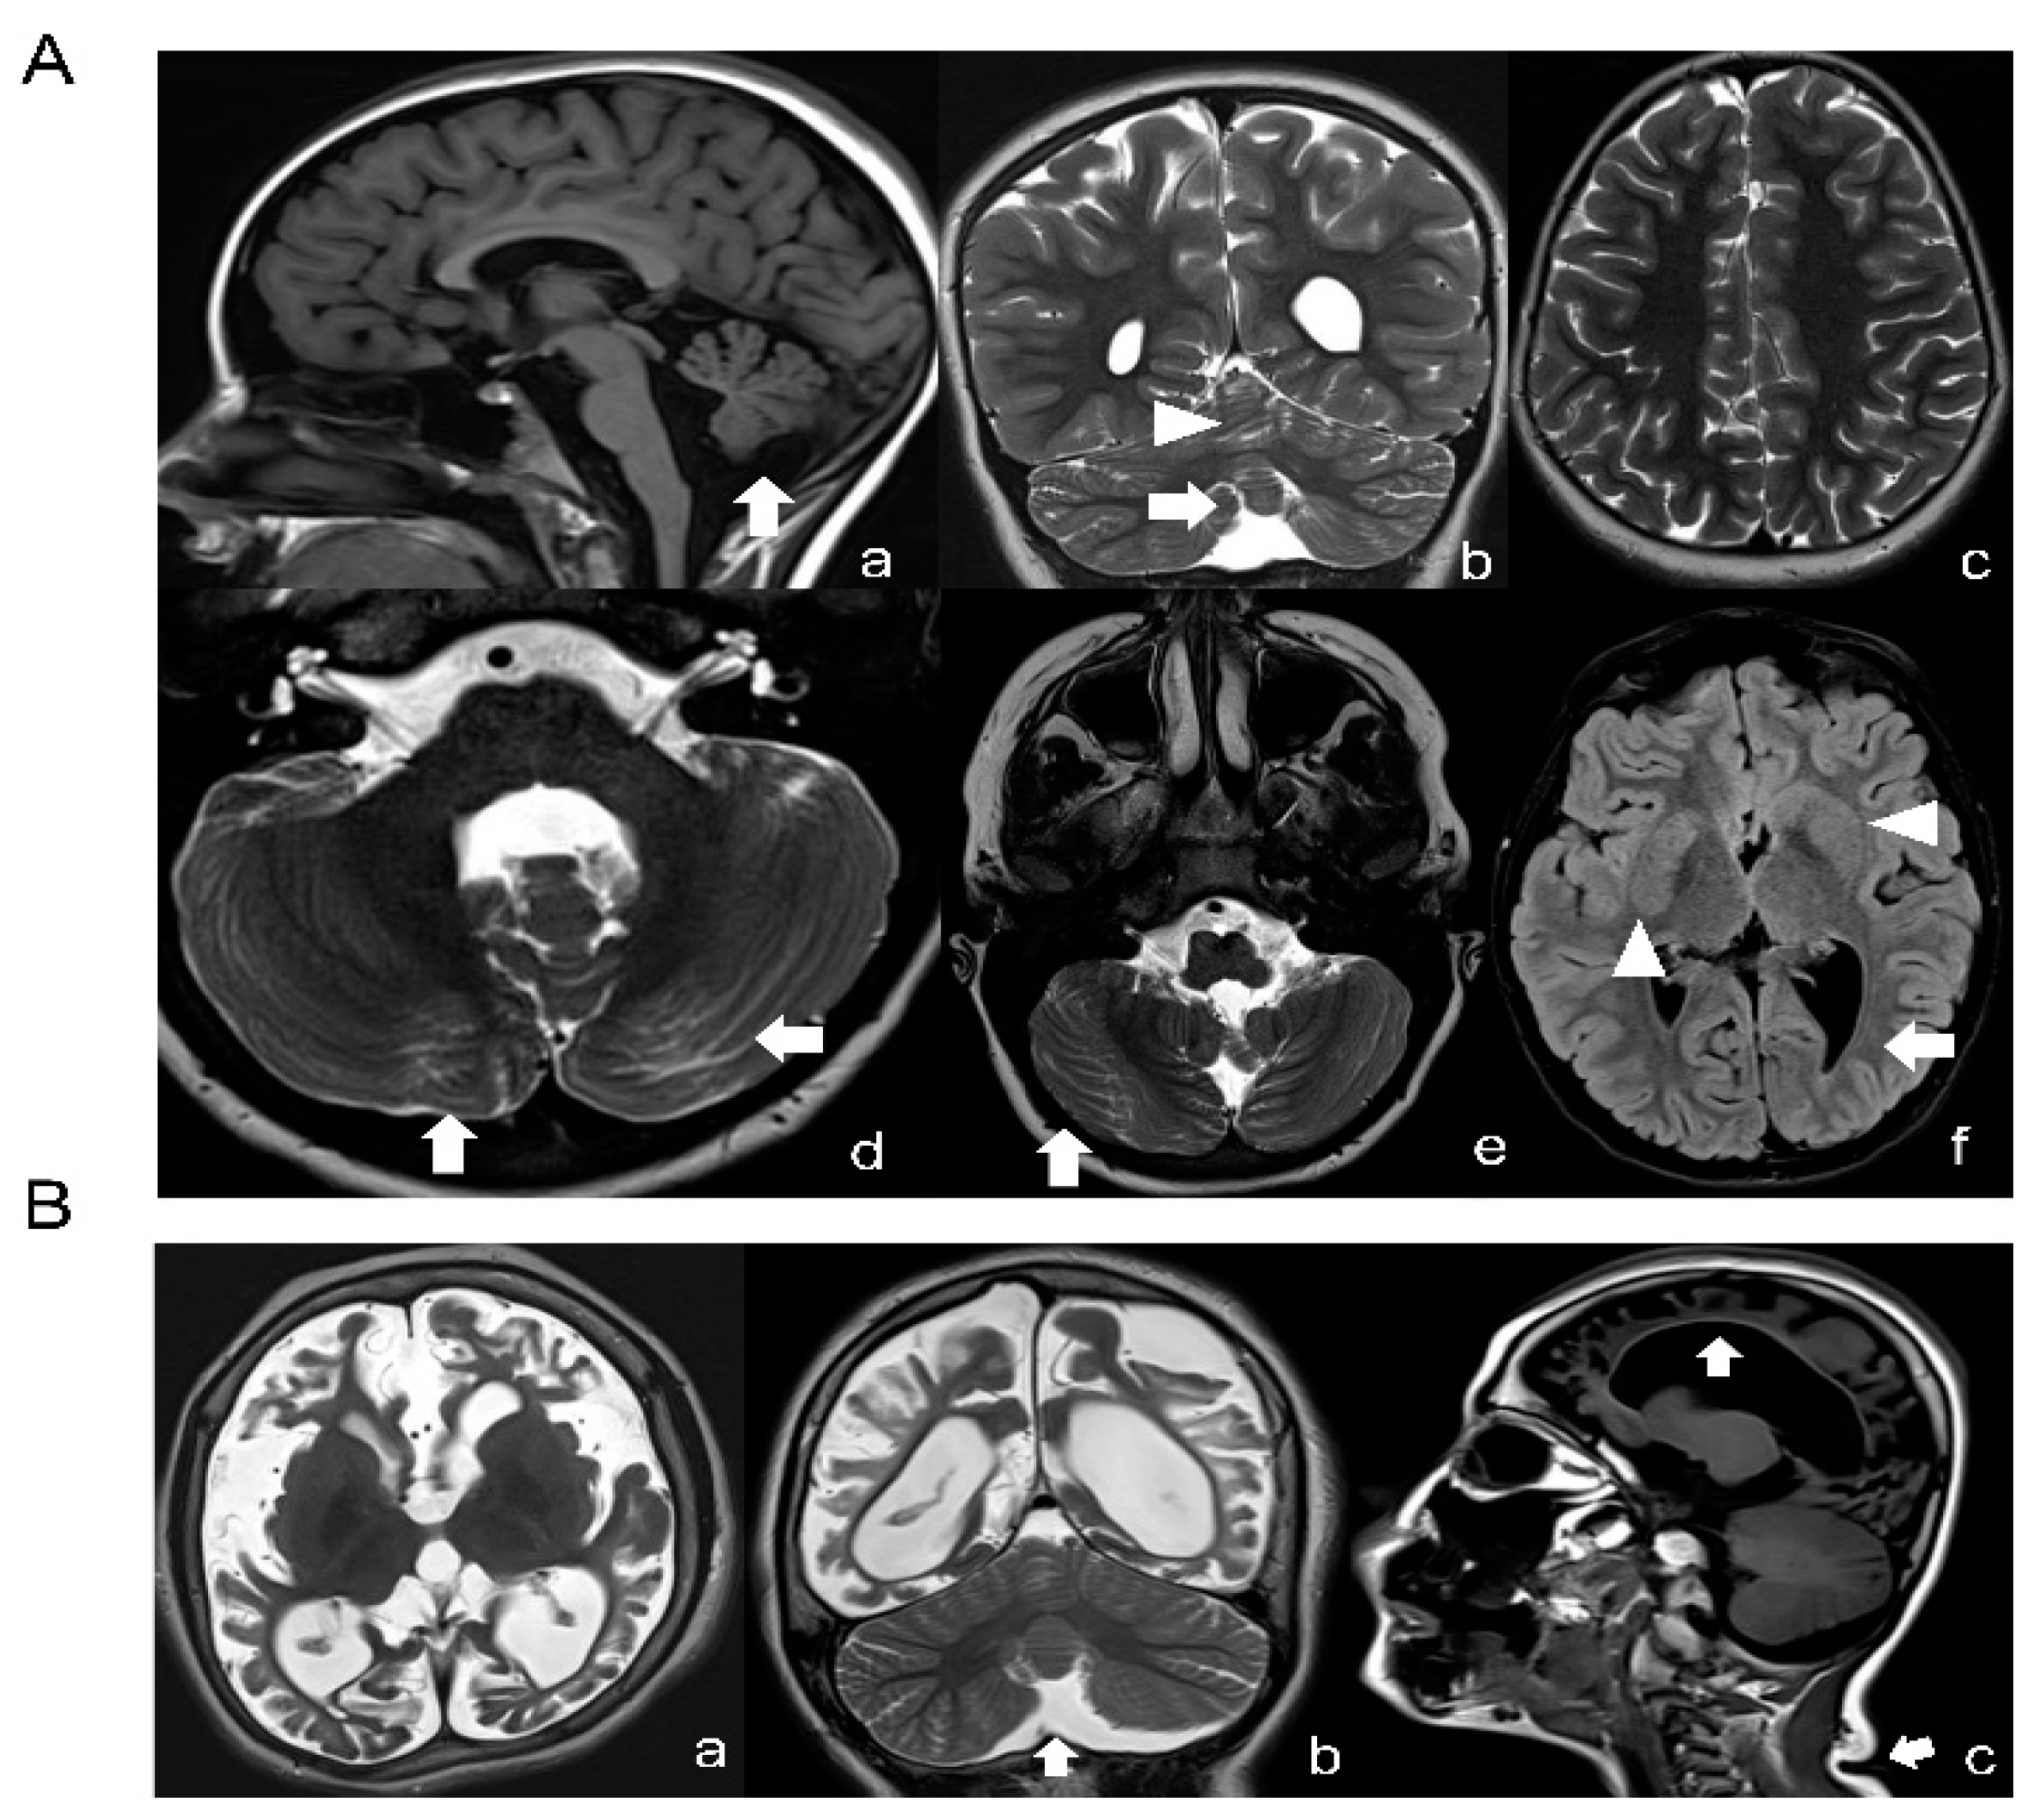

2.1. TUBB Gene Mutation Analysis